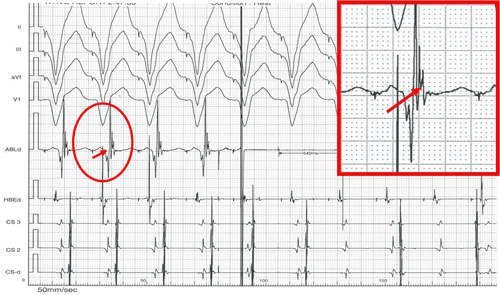

Hình 8: Triệt đốt đường dẫn truyền phụ điển hình trong lúc nhịp xoang. Kết quả xuất hiện ngay sau 372 ms (hết hình ảnh WPW), điện đồ vị trí đích (trong ô vuông đỏ) có sóng nhĩ đi trước và trộn lẫn với sóng thất.

Hình 9: Triệt đốt đường dẫn truyền phụ điển hình trong lúc tạo nhịp thất phải. Kết quả xuất hiện ngay sau 540 ms (xuất hiện hình ảnh phân ly thất-nhĩ), điện đồ vị trí đích (trong ô vuông đỏ) có sóng thất đi trước và sóng nhĩ đi ngay sát sau sóng thất.

Hình 12: Triệt đốt đường chậm. Điện đồ vị trí đích (trong ô vuông đỏ) hình ảnh sóng nhĩ nhiều thành phần, biên độ thấp đi trước sóng thất, tỉ lệ biên độ sóng nhĩ/thất là 1/5. Kết quả triệt đốt đường chậm thành công thể hiện bằng sự xuất hiện nhịp bộ nối gia tốc ngay sau khi phát năng lượng tần số radio.